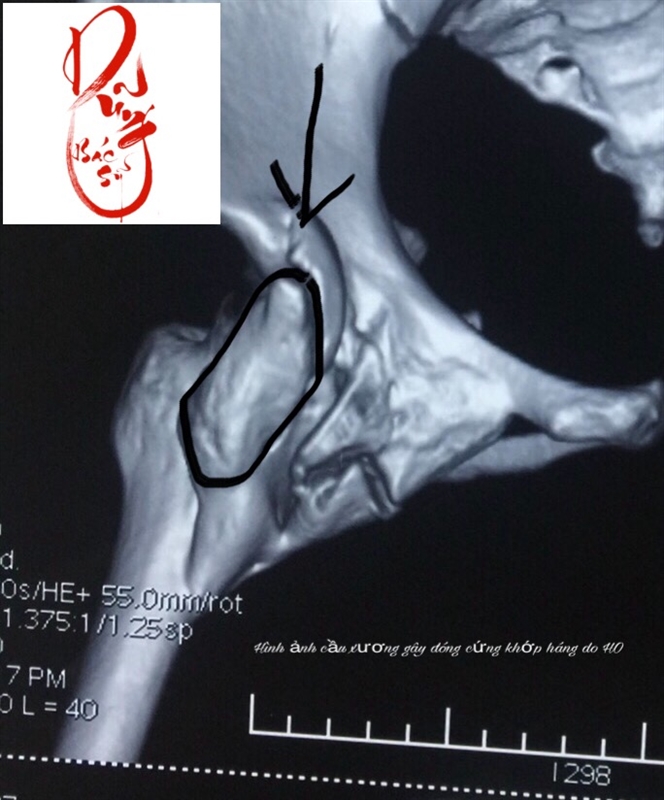

Cứng Khớp Háng Do Canxi Hóa Bất Thường Quanh Khớp

Can xi hoá bất thường Heterotopic ossification: (viết tắt là HO, tạm dịch là canxi hoá bất thường) là sự xuất hiện của cấu trúc xương ở mô mềm mà bình thường không có.HO xuất hiện thường sau các chấn thương xương khớp mô mềm, chấn thương tuỷ sống, bỏng hoặc chấn thương sọ não. […]